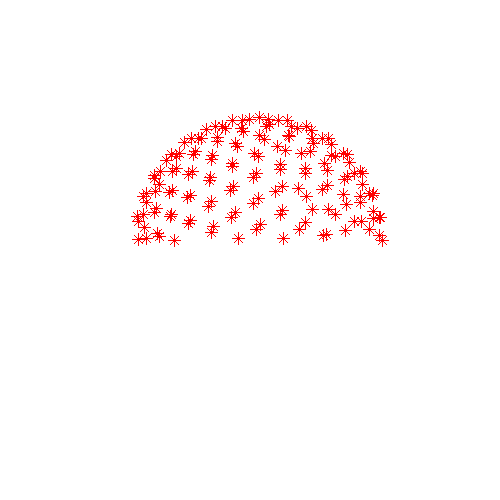

| Data sampled on the half-sphere | Data sampled on the whole-sphere |

![]() |

| The red dots corresponds to sample points on the diffusion sphere, *i.e.* they can be thought of as endpoints of a set of arrows starting at the origin and representing the diffusion gradients. The whole sphere on the right has been created by negating a subset of the vectors on the left. Hence they are identical w.r.t. sampling the diffusion signal. | |